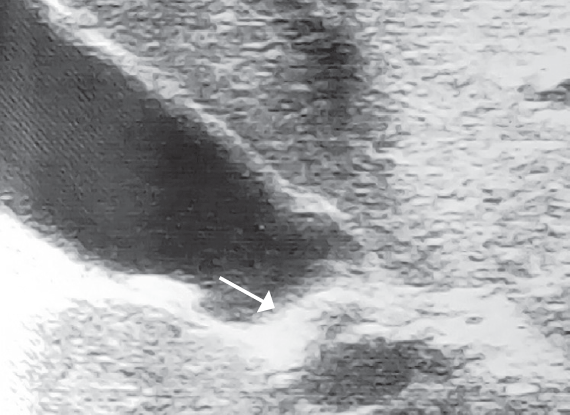

Для сравнения во вторую группу включили 140 детей с хроническим бескаменным холециститом. Возраст пациентов был от 2 до 17 лет. В 63,6 % случаев заболевание отмечено у девочек, соответственно у мальчиков — 36,4 %. Распределение по полу и возрасту в данной группе пациентов представлено в табл. 2. Всем пациентам было выполнено УЗИ желчного пузыря. У всех отмечалось утолщение и неоднородность стенки желчного пузыря. У 15 % выявлена деформация тела желчного пузыря (рис. 2). При этом ни у одного пациента не было патологических изменений в области пузырного протока.

Рис. 2. Деформация тела желчного пузыря

Fig. 2. Gallbladder deformation